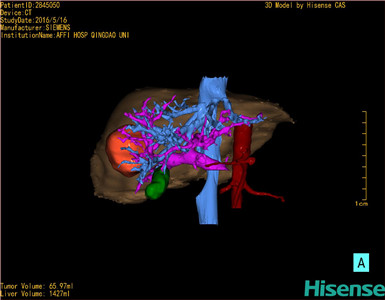

将0.625mm双源薄层CT资料的静脉期和动脉期Dicom格式文件导入海信CAS系统。

通过调节窗宽窗位调整CT序号,对肿瘤,肝实质,胆囊,下腔静脉,肿瘤,肝动脉、门静脉及肝静脉等进行三维重建;系统自动计算肿瘤体积和肝脏体积。

模拟手术操作,自动计算切除肿瘤体积。肝脏体积为1427ml,肿瘤体积为65.97ml,肿瘤体积为肝脏体积的4.6%,通过比对40-50岁正常肝脏体积为1368.38±279.24ml,通过术前模拟手术,精准判断切除后剩余肝脏体积能耐受,避免肝衰竭发生。

术前手术方案的规划。

术前三维重建:

重建图片